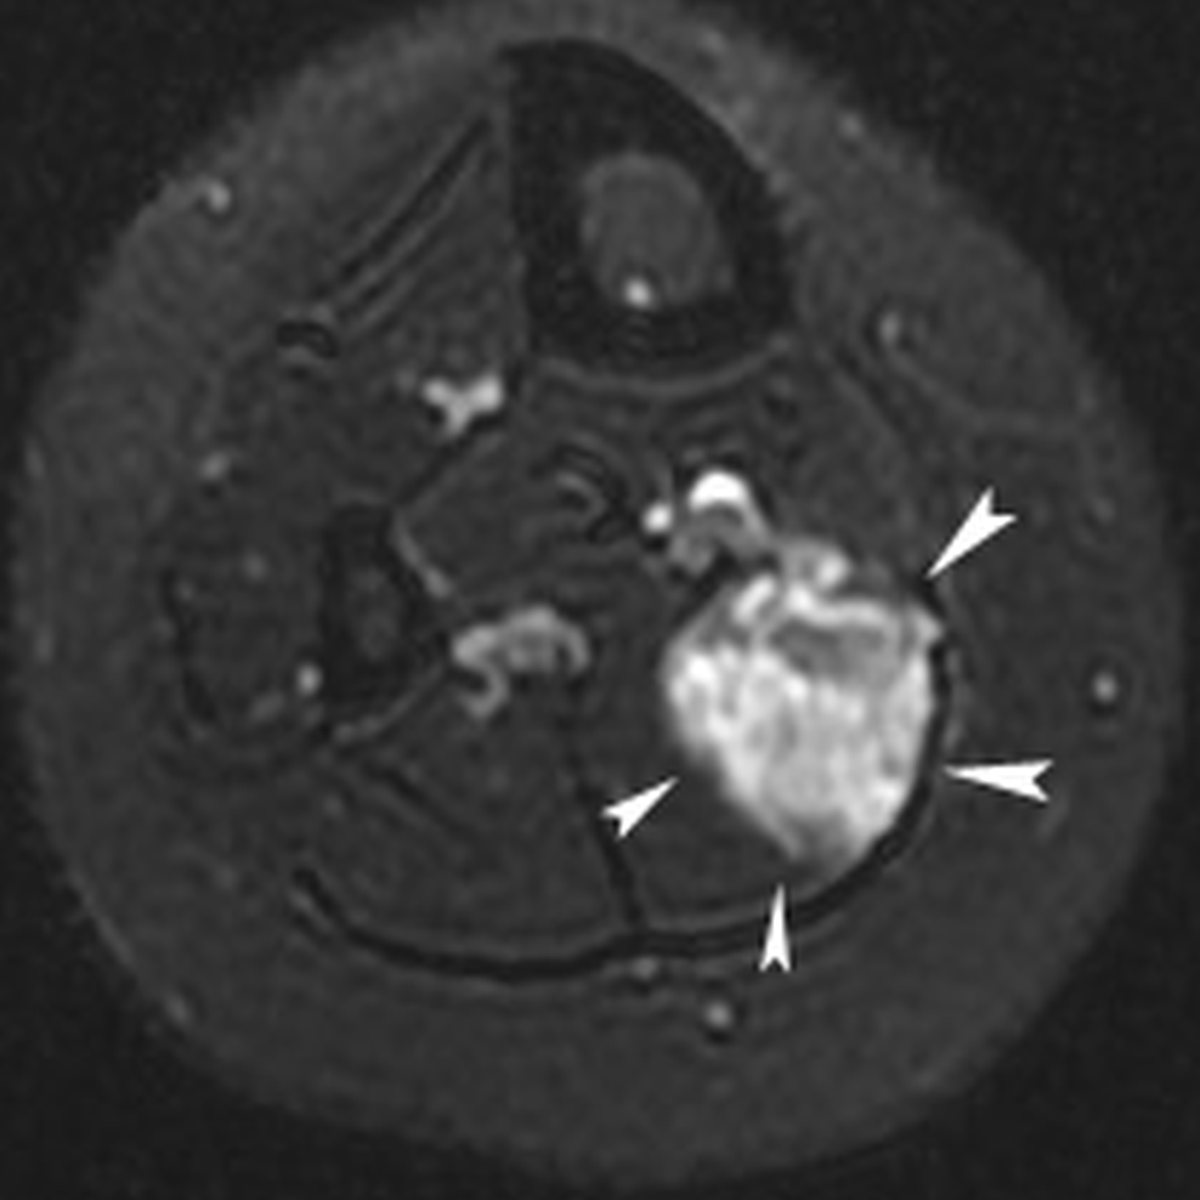

Patients were female and in between 11 and 20 years of age (median 16 years); the majority of patients presented with an intramuscular symptomatic VM with a median diameter of 2.9 cm at the lower limb (Figure 1a); two out of four patients previously underwent unsuccessful percutaneous sclerotherapy as summarized in Table 1.

Figure 1a

Twenty-year-old female with chronic calf pain. T2-weigthed axial magnetic resonance image of the calf demonstrating an hyperintense mass lesion with a maximal diameter of 3.6 cm (white arrowheads) in the right soleus muscle, suggestive for low-flow vascular malformation.